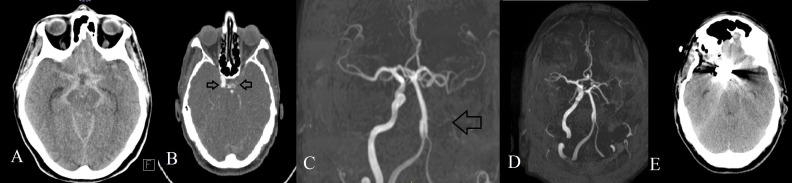

男性,67岁,突发头痛,意识下降,诊断为自发性蛛网膜下腔出血(SAH)。影像学显示前交通动脉(ACoA)动脉瘤和先天性左侧颈内动脉(ICA)缺失,颈动脉管缺失证实了这一点。动脉瘤通过手术切除。术后血管造影显示左侧大脑前动脉和中动脉经后循环侧支血流灌注。病人完全康复了。先天性ICA缺失是罕见的,但显著改变了脑血流动力学,特别是在威利斯周围,使患者易形成动脉瘤。该病例强调了血管成像对SAH患者的重要性,并强调了对先天性血管异常的紧急诊断和干预的必要性。

A 67-year-old male presented with sudden headache and decreased consciousness, diagnosed as spontaneous subarachnoid hemorrhage (SAH). Imaging revealed an anterior communicating artery (ACoA) aneurysm and congenital absence of the left internal carotid artery (ICA), confirmed by the absence of the carotid canal. The aneurysm was surgically clipped. Postoperative angiography demonstrated that the left anterior and middle cerebral arteries were perfused via collateral flow from the posterior circulation. The patient made a full recovery. Congenital ICA absence is rare but significantly alters cerebral hemodynamics, especially within the circle of Willis, predisposing patients to aneurysm formation. This case underlines the importance of vascular imaging in patients with SAH and highlights the need for urgent diagnosis and intervention in the presence of congenital vascular anomalies.